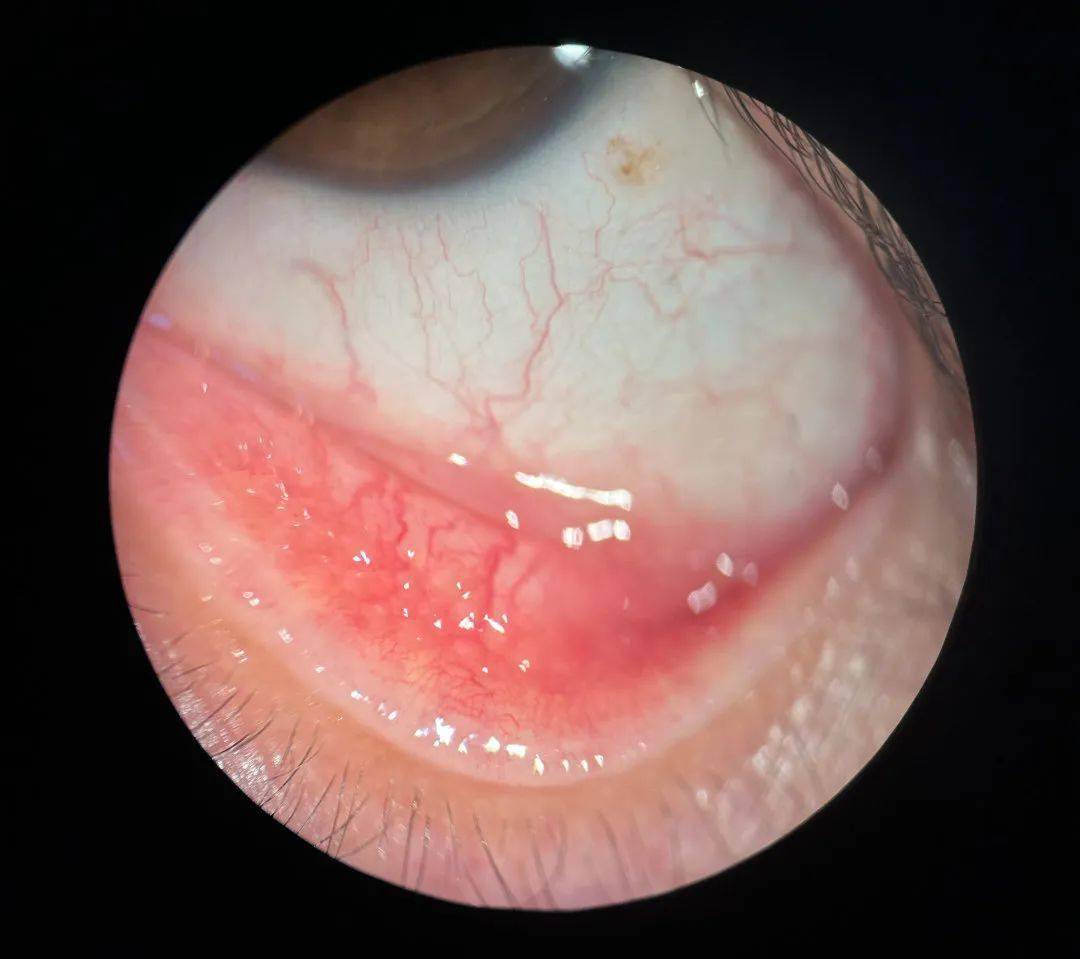

救我!我想把眼珠子抠出来!"入春后,你中招了吗?_杭州_过敏性_症状

图片尺寸1080x959